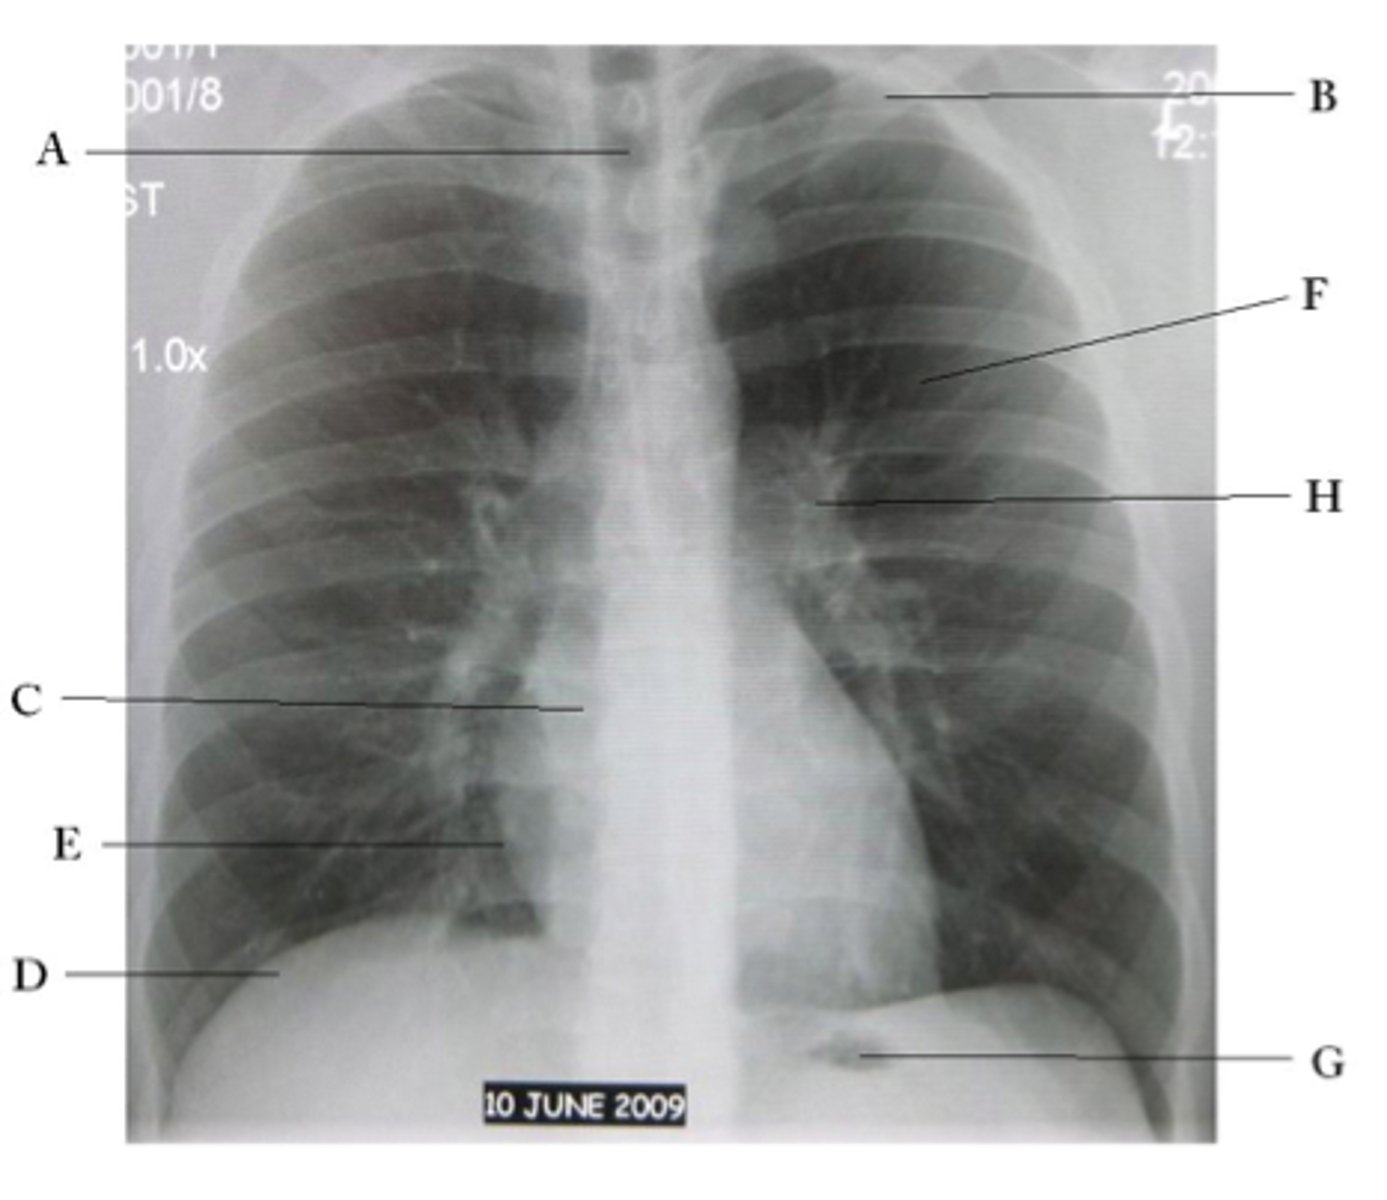

A

trachea

B

Clavicle

C

Right atrium

D

Diaphragm

E

Cardiophrenic angle

F

left upper lobe

G

gastric bubble

H

Left hilum